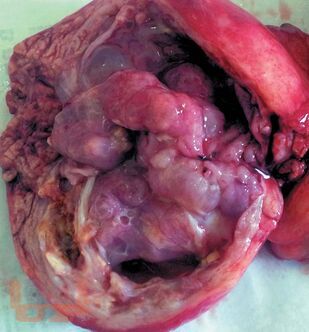

Описаны характерные морфологические признаки, приведены сведения о микроскопических и гистохимических маркерах различных вариантов кистозных опухолей, позволяющих определить их происхождение и прогнозировать дальнейшее течение. Отдельная глава посвящена дифференциальной диагностике кистозных опухолей с другими кистозными и опухолевыми поражениями поджелудочной железы.